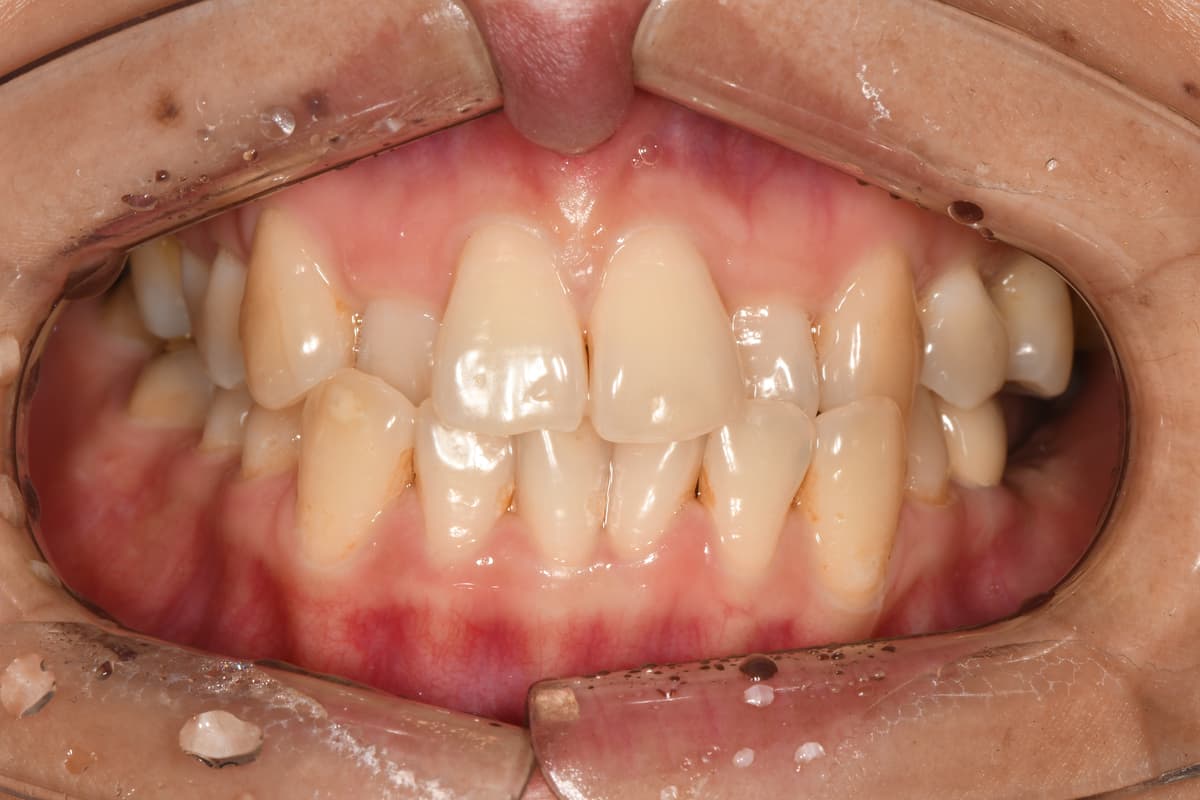

교정 치료 전후 사례

교정과 전문의가 직접 진료한

실제 환자 케이스입니다

김●● · 일반 교정

이●● · 심한 부정교합